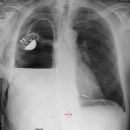

Sunshine C-Pulse Device